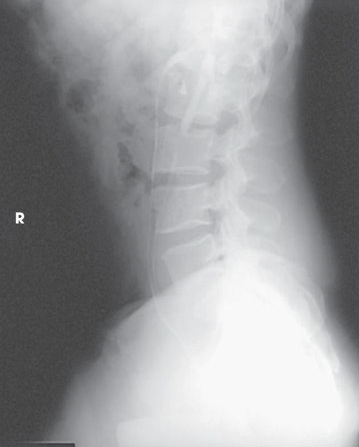

What is this projection

Right lateral